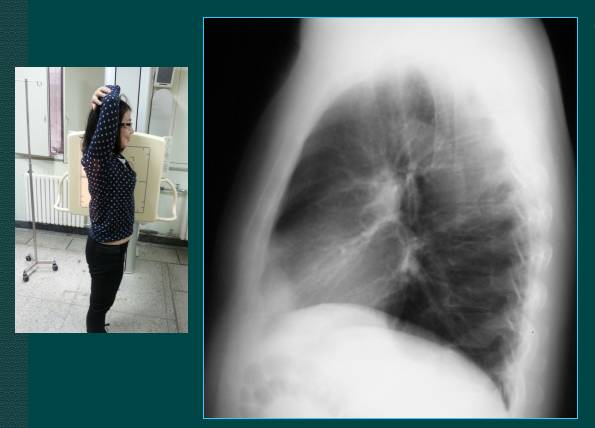

2. 胸部侧位片

上图是胸部侧位片的拍摄,一般采取右侧位拍片,如果看心脏影可以采取左侧位片。